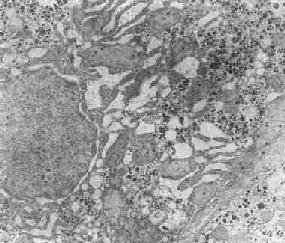

在由各種原因引起的細胞變性和壞死過程中,粗面內(nèi) 質(zhì)網(wǎng)的池一般出現(xiàn)擴張,較輕的和局限性的擴張只有在電鏡下才能窺見,重度擴張時則在光學顯微鏡下可表現(xiàn)為空泡形成,電鏡下有時可見其中含有中等電子密度的 絮狀物。在較強的擴張時,粗面內(nèi)質(zhì)網(wǎng)同時互相離散,膜上的顆粒呈不同程度的脫失。進而內(nèi)質(zhì)網(wǎng)本身可斷裂成大小不等的片段和大小泡(如下圖)。這些改變大 多見于細胞水腫時,故病變不僅見于內(nèi)質(zhì)網(wǎng),也同時累及Golgi器、線粒體和胞漿基質(zhì),有時甚至還累及溶解體。

肝細胞粗面內(nèi)質(zhì)網(wǎng)擴張